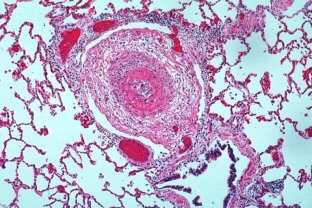

As mentioned above, in most situations, impaired renal function in periarteritis nodosa manifests itself in the primary vascular lesion. It is possible to identify certain signs of this by both macroscopic and light-optical research methods.

- Segmental vasculitis of the internal arteries of the kidneys can be detected by the light-optical method, which is also characterized by the alternation of healthy and disturbed sections of the vessels. In many cases, damage to the walls of blood vessels is also noted. A characteristic disorder in periarteritis nodosa can also be the simultaneous presence of both acute and chronic changes in the vessels.